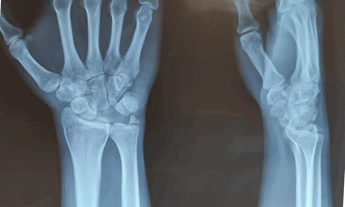

Рис. 1. Рентгенограммы кистевого сустава пациента из группы 1 через 6 месяцев после травмы. Последствия закрытого вправления перилунарного повреждения. Определяются ладьевидно-перилунарная диссоциация, признаки подвывиха ладьевидной кости, субхондральный склероз костей запястья и дистального метаэпифиза лучевой кости

В группе 2 на рентгенограммах через 3, 6 и 12 месяцев во всех наблюдениях наблюдалось снижение суставной щели в лучезапястном, среднезапястном и запястно-пястном суставах [в среднем 1,5 мм (± 0,1)] и неравномерность ладьевидно-полулунного и полулунно-трехгранного промежутков. Нарушение целостности запястных арок наблюдалось в 10 (83,3%) случаях (рис. 2). На МРТ у 10 (83,3%) пациентов были выявлены признаки асептического некроза полулунной кости.

Рис. 2. Рентгенограммы кистевого сустава пациента из группы 2 через 6 месяцев после закрытого вправления вывиха с фиксацией спицами. Определяются подвывих ладьевидной кости и ладьевидно-полулунная диссоциация и признаки развития деформирующего артроза лучезапястного сустава 1-2 ст.